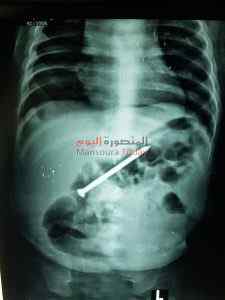

صرح الدكتور أحمد الرفاعى مدير مستشفى الأطفال بجامعة المنصورة عن تمكن فريق جراحى بوحدة الجهاز الهضمى بمستشفى الأطفال بجامعة المنصورة من اجراءعملية استخراج مسمار طوله 6 سم ، باستخدام المنظار بدون اى جرح أو مضاعفات أو تدخل جرحى من بطن طفل عمره ٩شهور .

وأشار الدكتور محمد عز الرجال أن الطفل كان يلعب مع أخوه ٣سنوات ، فى عدم وجود الام بعدها جاء الطفل الكبير يخبر الأم أن الطفل الصغير بلع مسمار .

وقامت الأم خلال ستة أيام بمحاولة استخراج المسمار طبيا ، حتى جاءت مستشفى الاطفال الساعة التاسعة صباحا ، وتم عرض الحالة على الفريق الطبى وتم إجراء الأشعة لتحديد مكان المسمار وقرر الفريق استخراجه باستخدام المنظار وتمت العملية بسلام من غير مضاعفات والطفل غادر المستشفى فى نفس اليوم .